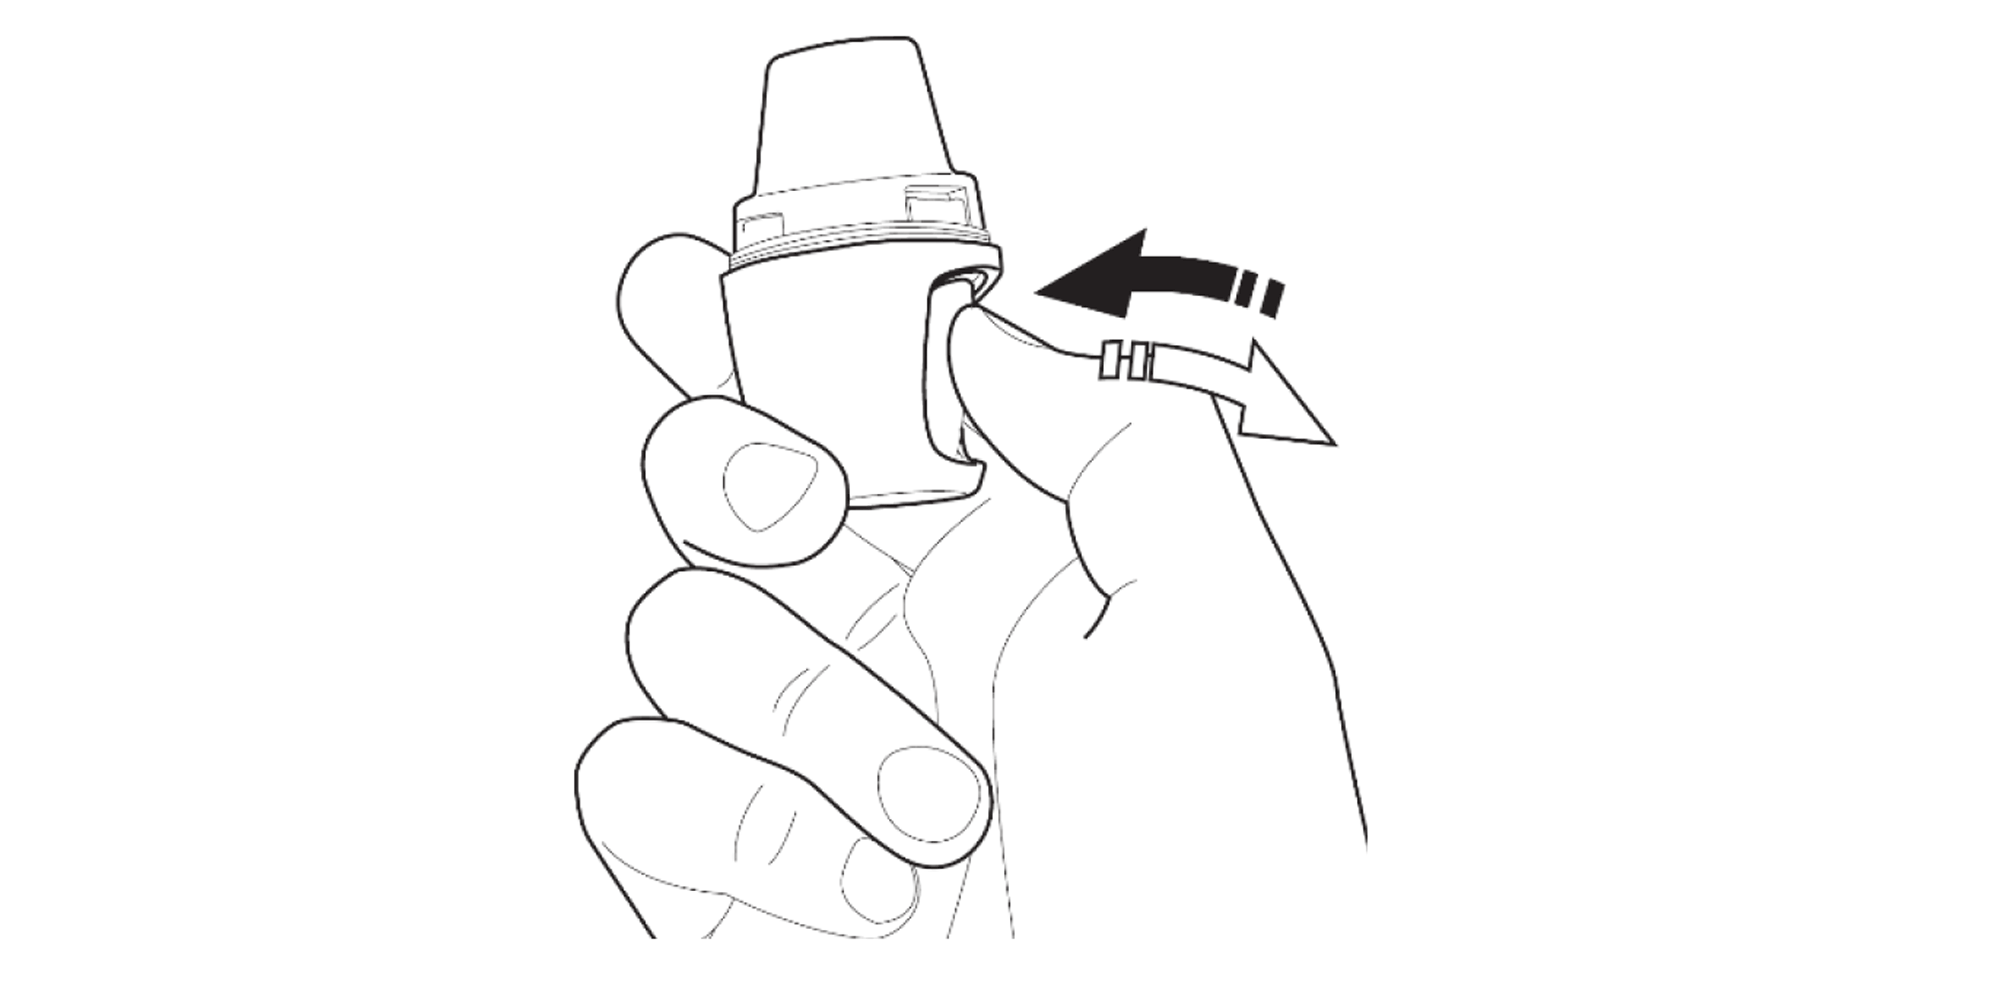

Press the area marked with a chevron. Pull the mouthpiece up and away from the base.

Firmly press the mouthpiece closed until you hear a click.

With the mouthpiece facing upwards, fully press the button in and release. Only press the button once!